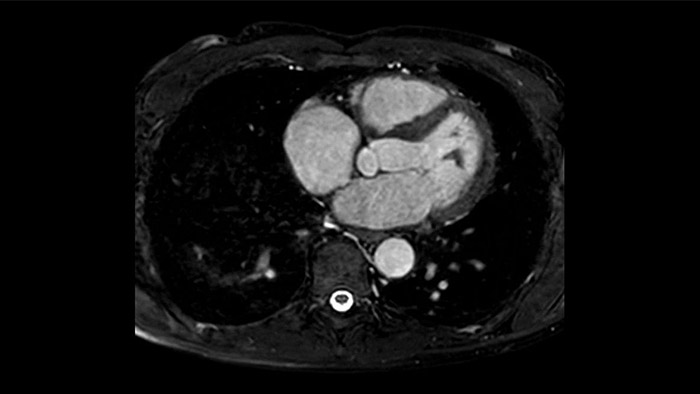

L'utilità diagnostica e prognostica della RM cardiaca è in continua crescita. È possibile valutare l'anatomia e la funzionalità cardiache utilizzando acquisizioni cine, ottenere informazioni sulla perfusione e vitalità del tessuto cardiaco, visualizzare potenziali edema con la sequenza Black Blood, accedere e persino quantificare la caratterizzazione dei tessuti con CardiacQuant.

IntelliSpace Portal offre Comprehensive Cardiac RM Suite che fornisce flussi di lavoro dedicati per analisi funzionale, vitalità del miocardio, LGE, valutazione della mappatura cardiaca e analisi funzionale dei ventricoli destro e sinistro in meno di 5 minuti per caso1.